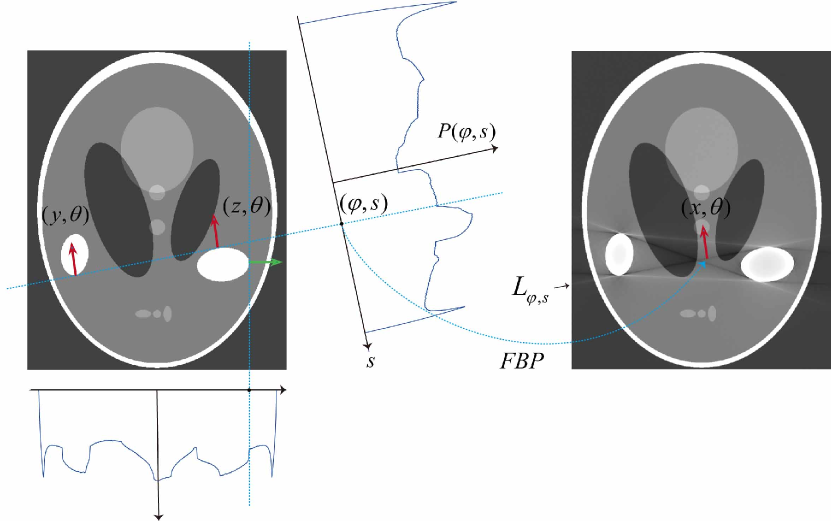

where with being the angle in (26) Hormander1983 ; Oneill2006 ; Quinto2006 . Then is the straight line containing two points and as shown in Fig. 2.

Fig. 3 illustrates how streaking artifacts are produced by the geometric structure of . In Fig. 3, is given by so that contains the line segments and . Using arguments in the proof of Theorem 3.1, we have

Hence, the lines and can be included in . Fig. 3 shows that the lines and are streaking artifacts.

| (36) |

only when if the metal region is not strictly convex. In other words, the streaking artifacts in are related with the geometry of , as shown in Fig. 4. In the figure, we use the Shepp-Logan phantom as and the homogeneous metallic objects with the various geometries are added to illustrate the streaking artifacts in the reconstructed image .

According to Theorem 3.1 and Proposition 1, metal streaking artifacts are due to the severe nonlinearity of the X-ray data with respect to the geometry of the metallic subject . Metal streaking artifacts are included in the union of tangent space , which is a tangent space of another point . In the case of single metallic object with a strictly convex boundary, the reconstructed CT image has no streaking artifact. If consists of two simply connected domains and with boundaries respectively, there are four different tangent lines touching both the metal domains and .